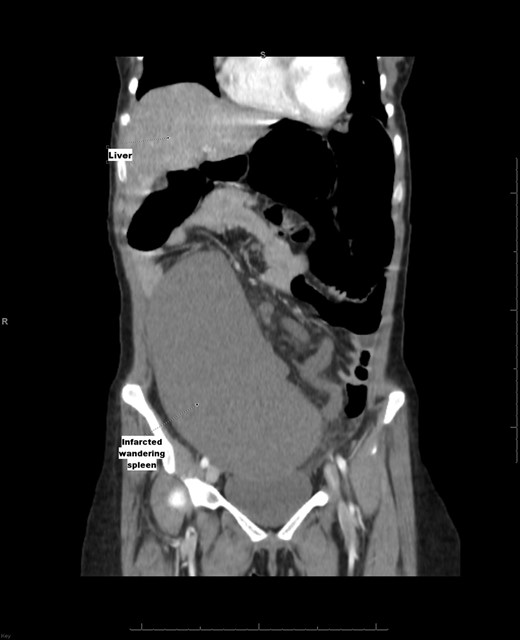

Laboratory investigation showed a white blood cell count of 15.13 × 103/UL, (mainly neutrophilia of 90.3%), a hemoglobin level of 9.4 g/dL, and a platelet count of 189 × 103/UL. The other biochemical parameters including liver enzymes were normal apart from a trace of jaundice, with total Bilirubin of 2.43 mg/dL and direct Bilirubin of 0.45 mg/dL. Chest X-ray showed bowel loops at the splenic fossa (Fig. 1). An initial diagnosis of a torted ovarian cyst was made. A pelvi-abdominal ultrasound revealed normal adnexa but a right-sided soft pelvic-abdominal mass with the absence of a splenic shadow at the left hypochondrium. Subsequently, CT scan of the abdomen and pelvis revealed a large right-sided infarcted spleen of 30 × 16 × 10 cm3 (Fig. 2) and a ‘whirl sign’ of the splenic pedicle (Fig. 3). Furthermore, CT scan showed signs of portal hypertension (Fig. 4) associated with mesenteric varices (Fig. 5). The patient subsequently underwent a surgical exploration.

Computed tomography of the abdomen and pelvis with IV contrast shows a non-enhancing (infarcted) spleen (dotted arrow) that has completely migrated to the right side of the abdomen and pelvis.